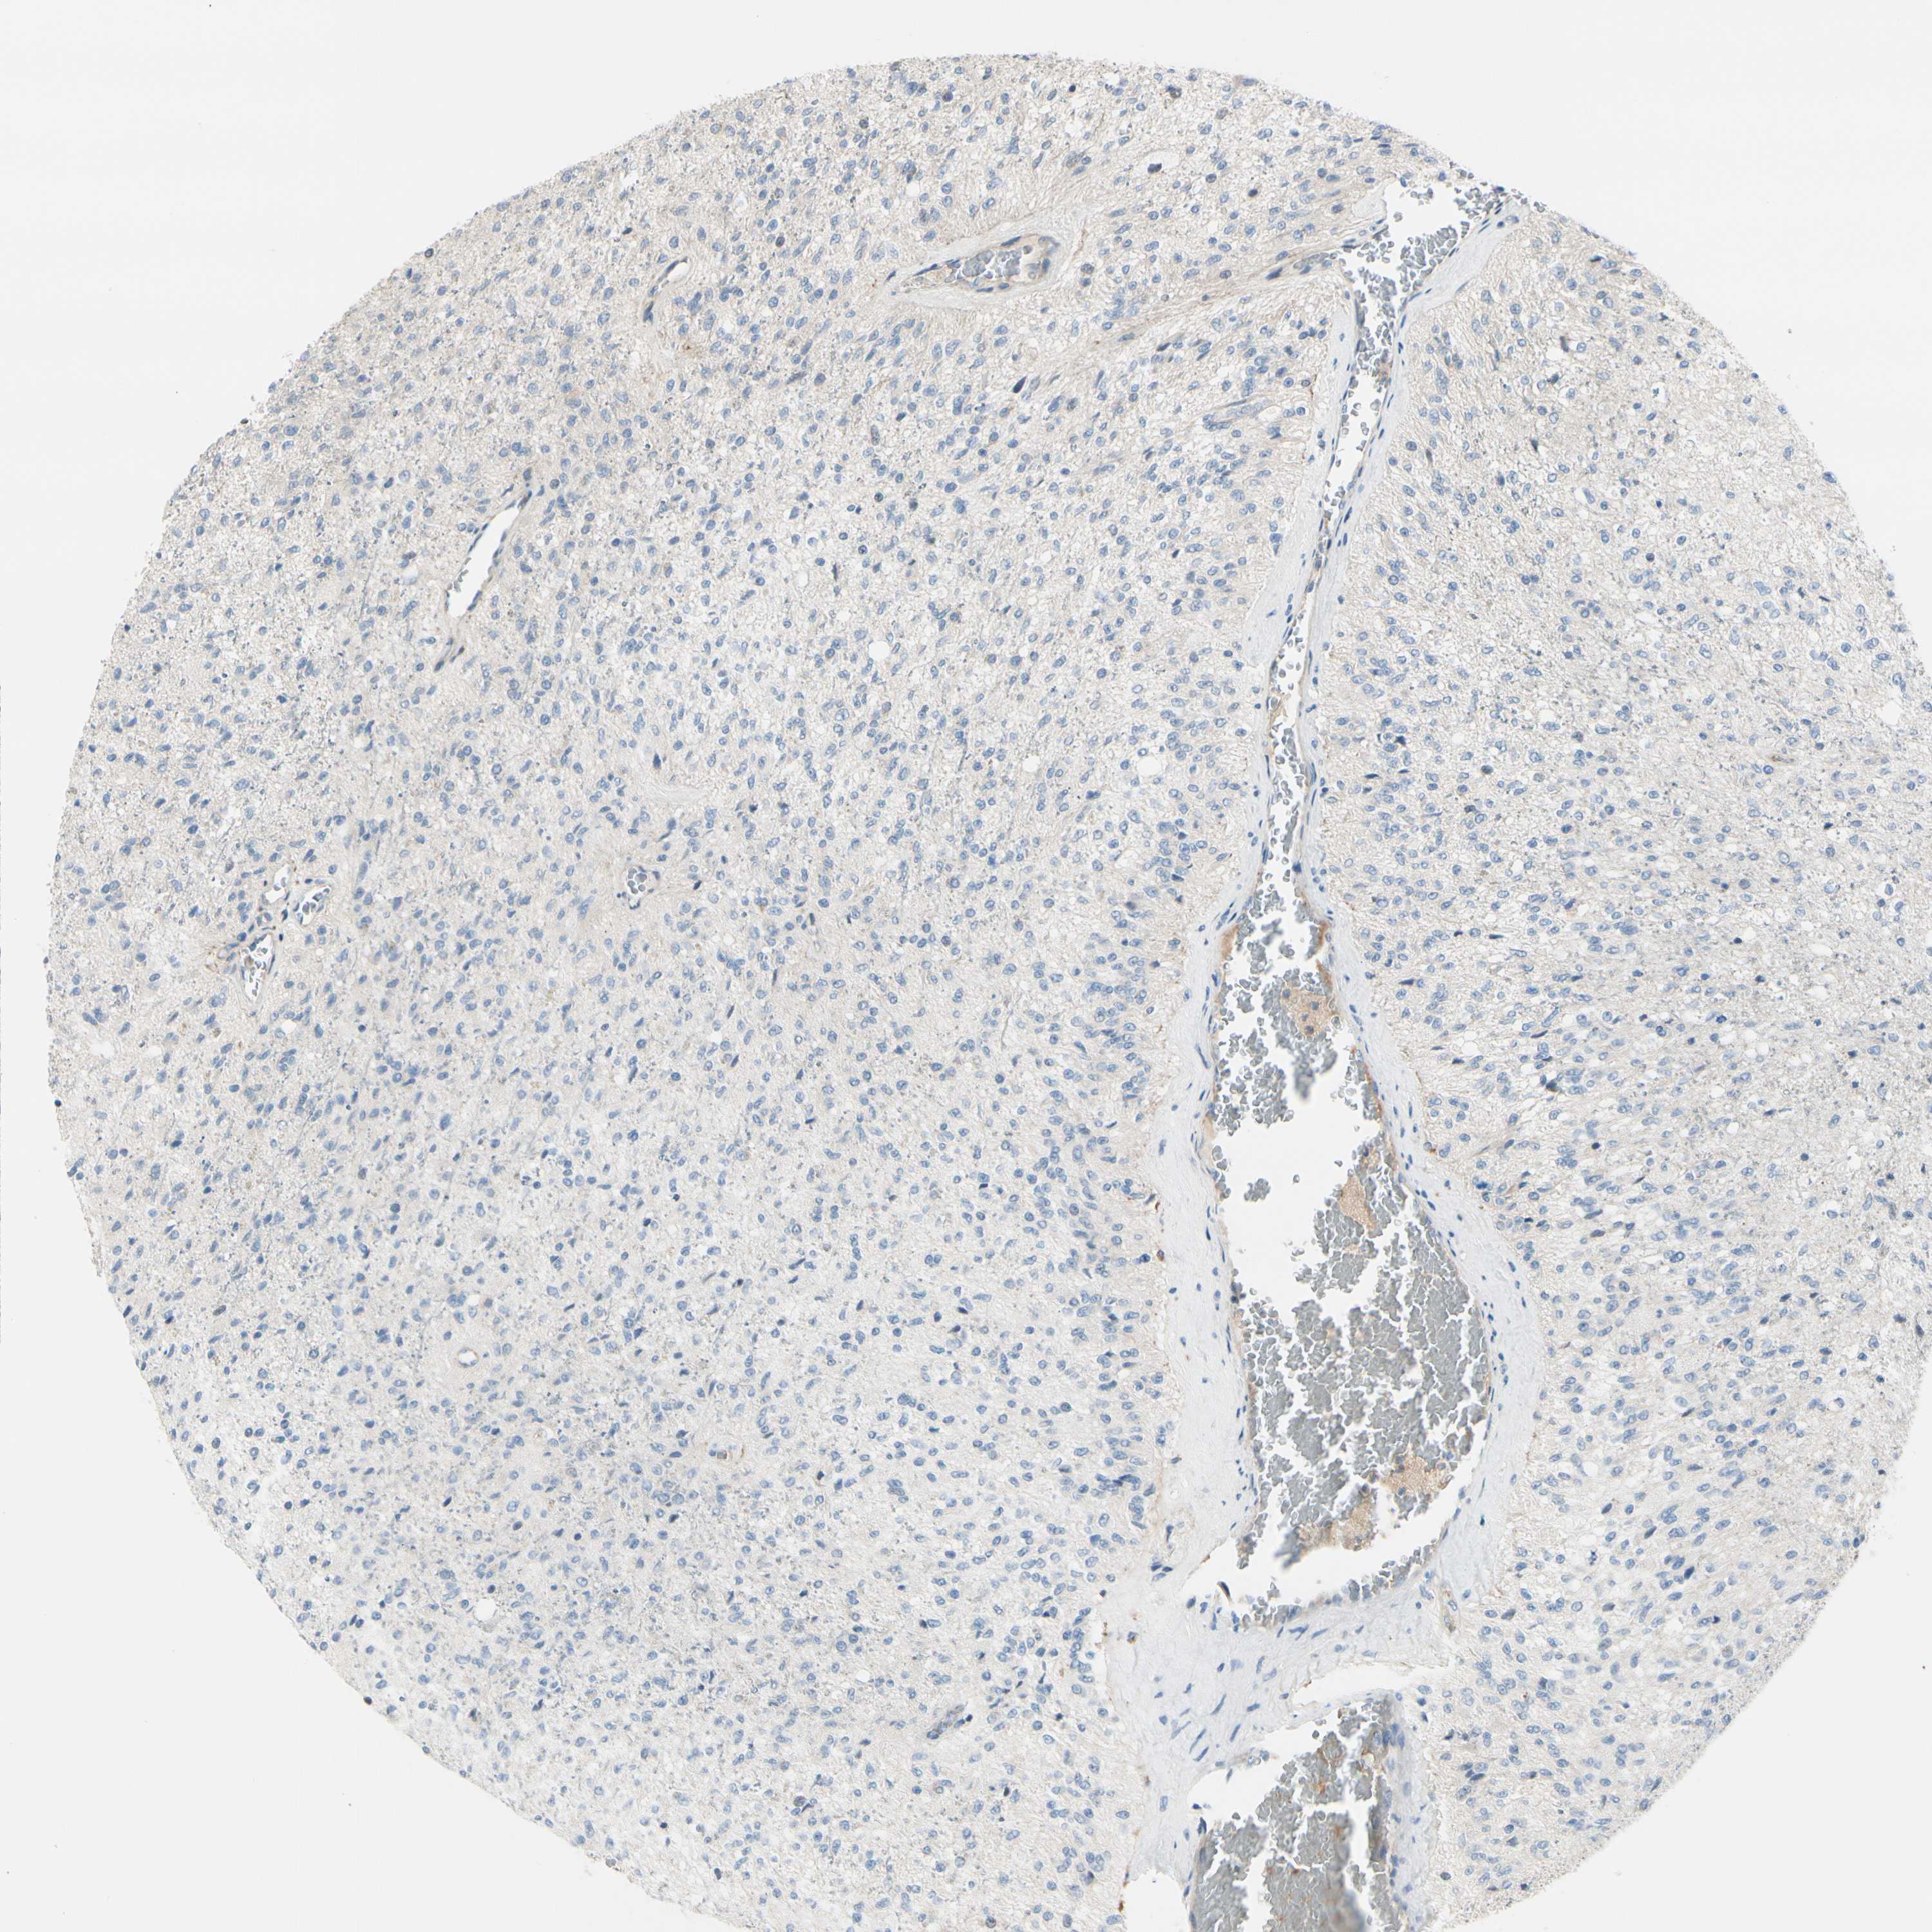

GLIOMA - Protein expressioni

A mouse-over function shows sample information and annotation data. Click on an image to view it in a full screen mode. Samples can be filtered based on level of antibody staining by selecting one or several of the following categories: high, medium, low and not detected. The assay and annotation is described here.

Note that samples used for immunohistochemistry by the Human Protein Atlas do not correspond to samples in the TCGA dataset.

Antibody stainingi

Antibody staining in the annotated cell types in the current human tissue is reported as not detected, low, medium, or high, based on conventional immunohistochemistry profiling in selected tissues. This score is based on the combination of the staining intensity and fraction of stained cells.

Each image is clickable and will lead to virtual microscopy that enables deeper exploration of all samples and also displays staining intensity scores, fraction scores and subcellular localization as well as patient and tissue information for each sample.

Antibody HPA001636

Antibody HPA001637

Antibody CAB010822

Staining

High

Medium

Low

Not detected

Intensity

Strong

Moderate

Weak

Negative

Quantity

>75%

75%-25%

<25%

None

Location

Nuclear

Cytoplasmic/membranous

Cytoplasmic/membranous,nuclear

Glioma, malignant, High grade

Glioma, malignant, Low grade

Glioma, malignant, NOS